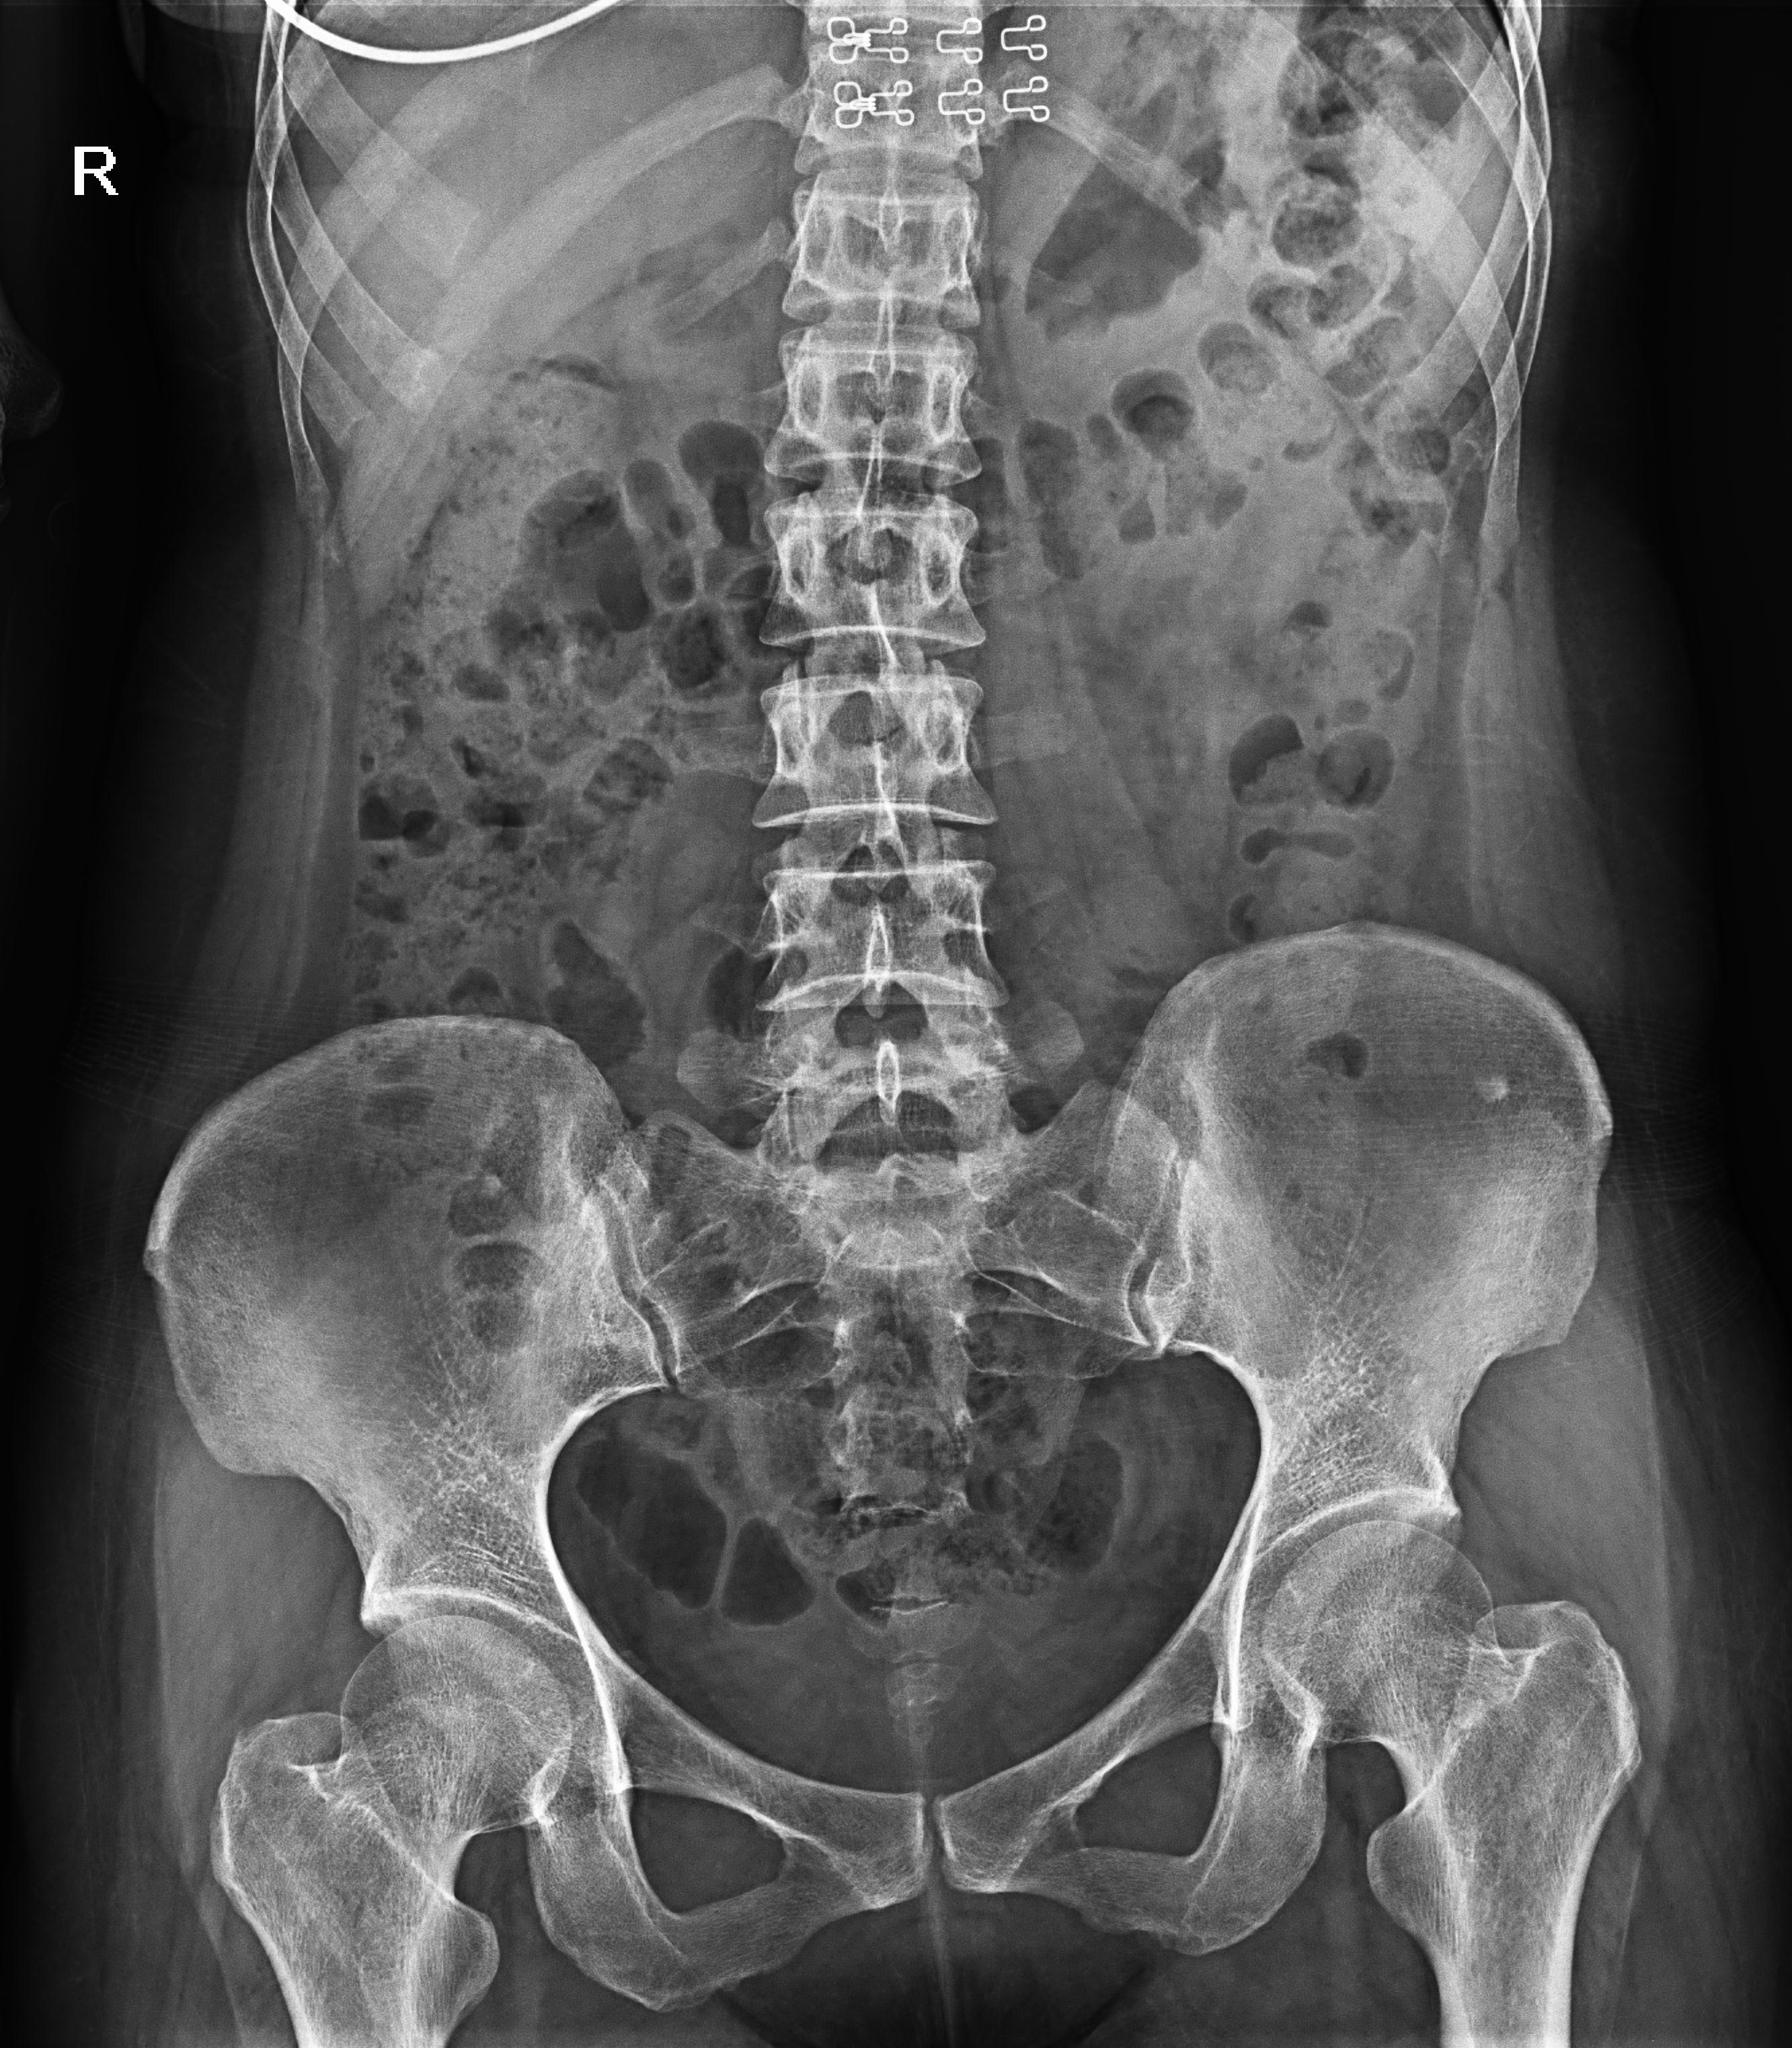

普利德醫(yī)療自主研發(fā)的新一代數(shù)字化X線透視攝影系統(tǒng),可應(yīng)用于DR攝影、數(shù)字透視、數(shù)字造影以及可視化精準DR拍片等多種臨床X線檢查領(lǐng)域。

● 17*17英寸的超高清像素動態(tài)平板探測器,更大的視野范圍,無需移動即可觀察整個動態(tài)過程,避免拖尾、噪聲對圖像的影響;

● 高效動態(tài)平板技術(shù),圖像不會有幾何畸變,提供高分辨率和精確的圖像,為醫(yī)生臨床診斷提供精準依據(jù);

● 最高幀速可達30幀/秒,動態(tài)采集清晰流暢,避免漏診、誤診情況的發(fā)生;

● 在可視過程或回放過程中,如發(fā)現(xiàn)疑似病灶,可進行毫秒級高清點片,隨時抓取單幀圖像,精準捕抓病灶。